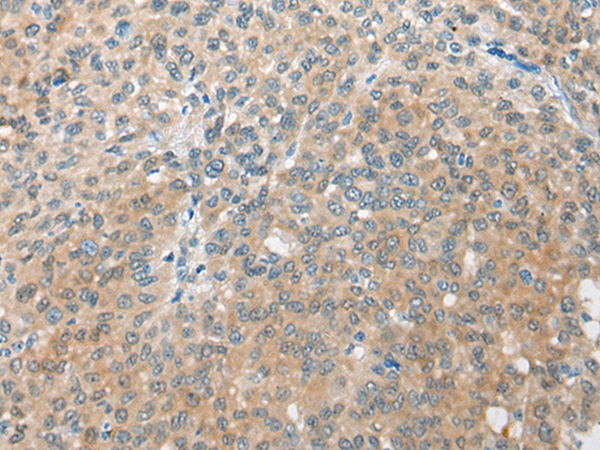

分类: 科研抗体货号: P09446别名:应用: IHC反应种属: Human, Mouse

分类: 科研抗体货号: P09445别名: HSPC065应用: IHC反应种属: Human, Mouse